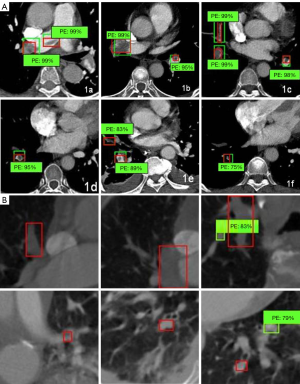

We divided 43 study groups of CTA 512×512 pictures into training sets (1,992 sheets) and test sets (192 sheets). The 101×101 embolism distribution block diagram was divided into a training set (13,144 sheets) and a test set (313 sheets), as shown in Figure 1A,B. Through the deep learning model of data learning and analysis, the final training was to obtain a prediction model. The test set was then tested. The results of the experiment are shown in Table 1.